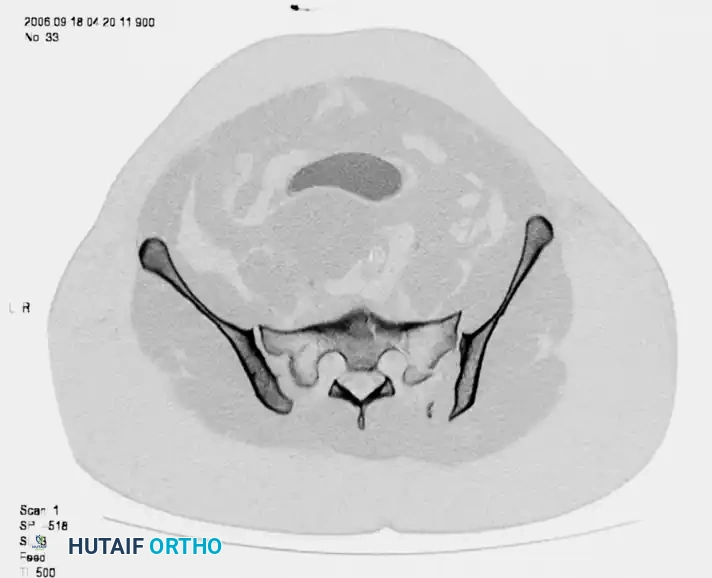

Tile and Young-Burgess Classifications

The Tile classification assesses stability, dividing injuries into rotationally and vertically stable (Type A), rotationally unstable but vertically stable (Type B), and rotationally and vertically unstable (Type C).

Image

FIGURE 56-49: A, Tile type B1 pelvic injury demonstrating diastasis of the pubic symphysis and anterior widening of the sacroiliac joint. B, CT scan confirming that the posterior sacroiliac joint ligaments remain intact.